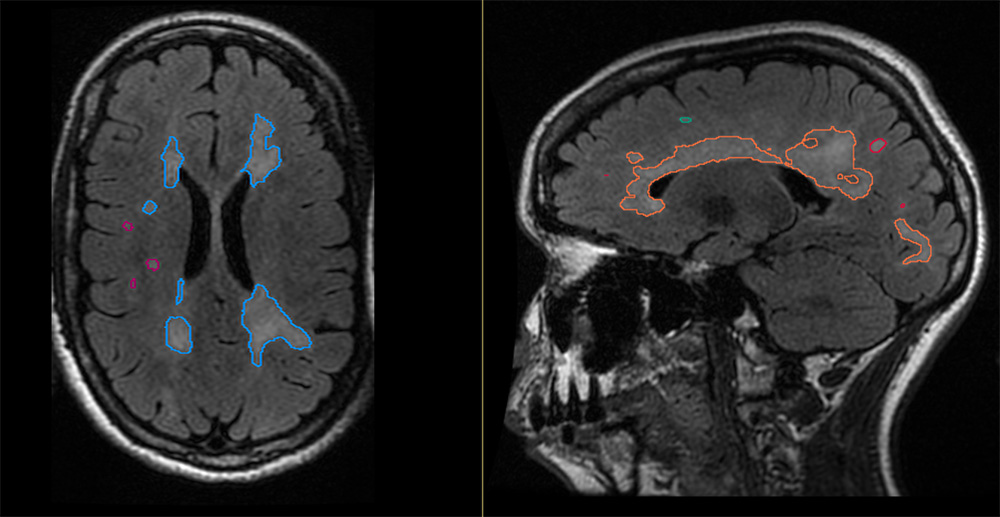

AI-powered WMH detection & segmentation

Provides consistent, automated localization of WMHs and segmentation of the boundaries for accurate assessment.

Creates efficient workflows with color-coded overlays on FLAIR images with seamless PACS integration that enables immediate visual assessment.

Provides automated segmentation and objective assessment of total WMH volume, lesion count, and anatomical distribution.